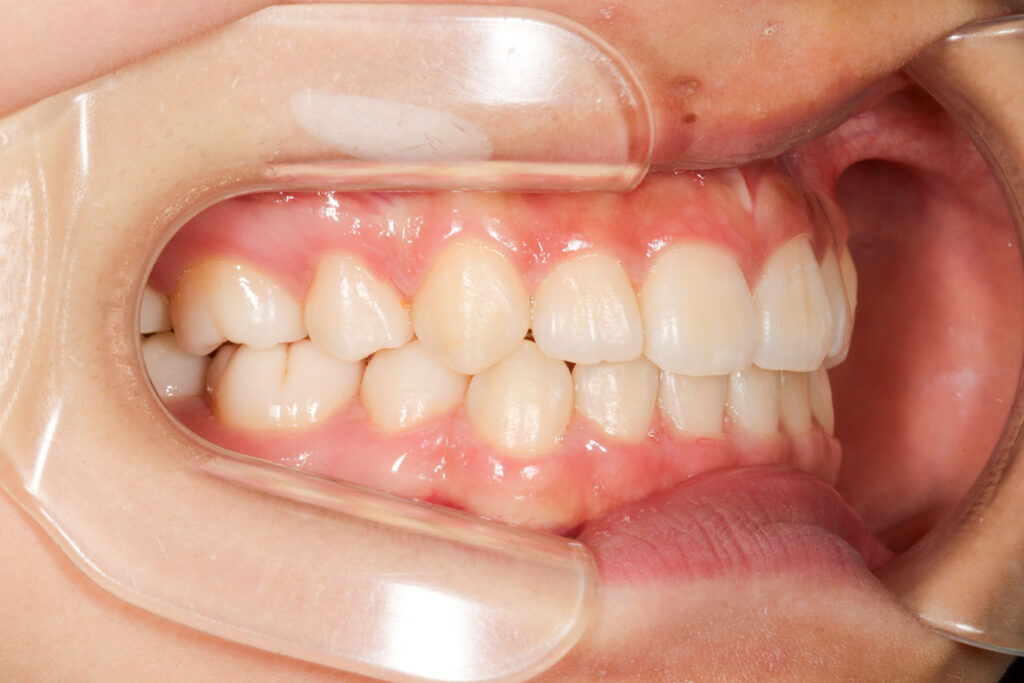

Before

After

年齢 10代

治療装置 表側の矯正装置(ホワイトコース)

治療内容 上下左右4本抜歯

治療期間 2年1か月

リスク 歯の移動に伴う痛み、歯肉退縮、歯根吸収、歯肉炎、虫歯

主訴 ガタガタが気になる

症状 叢生(ガタガタ)

治療回数 25回程度

総額費用 105万円程度